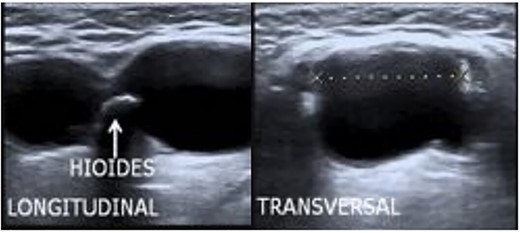

The ultrasound (Fig. 1) showed a soft tissue mass (13.7 ml) with multiple small calcific densities at the submandibular level with thick septations separating the locules and arterial vascularity of the solid component. A neck ultrasound demonstrated a bilateral thyroid enlarged (right lobe 5 × 3 × 1.5, left lobe 4.5 × 2 × 1.2 cm). There were also enlarged cervical lymph nodes in levels III (right) and IV (left). The fine-needle aspiration (FNA) was performed on the suspected thyroglossal duct. The biopsy suggested metastasis of thyroid cancer (TC).